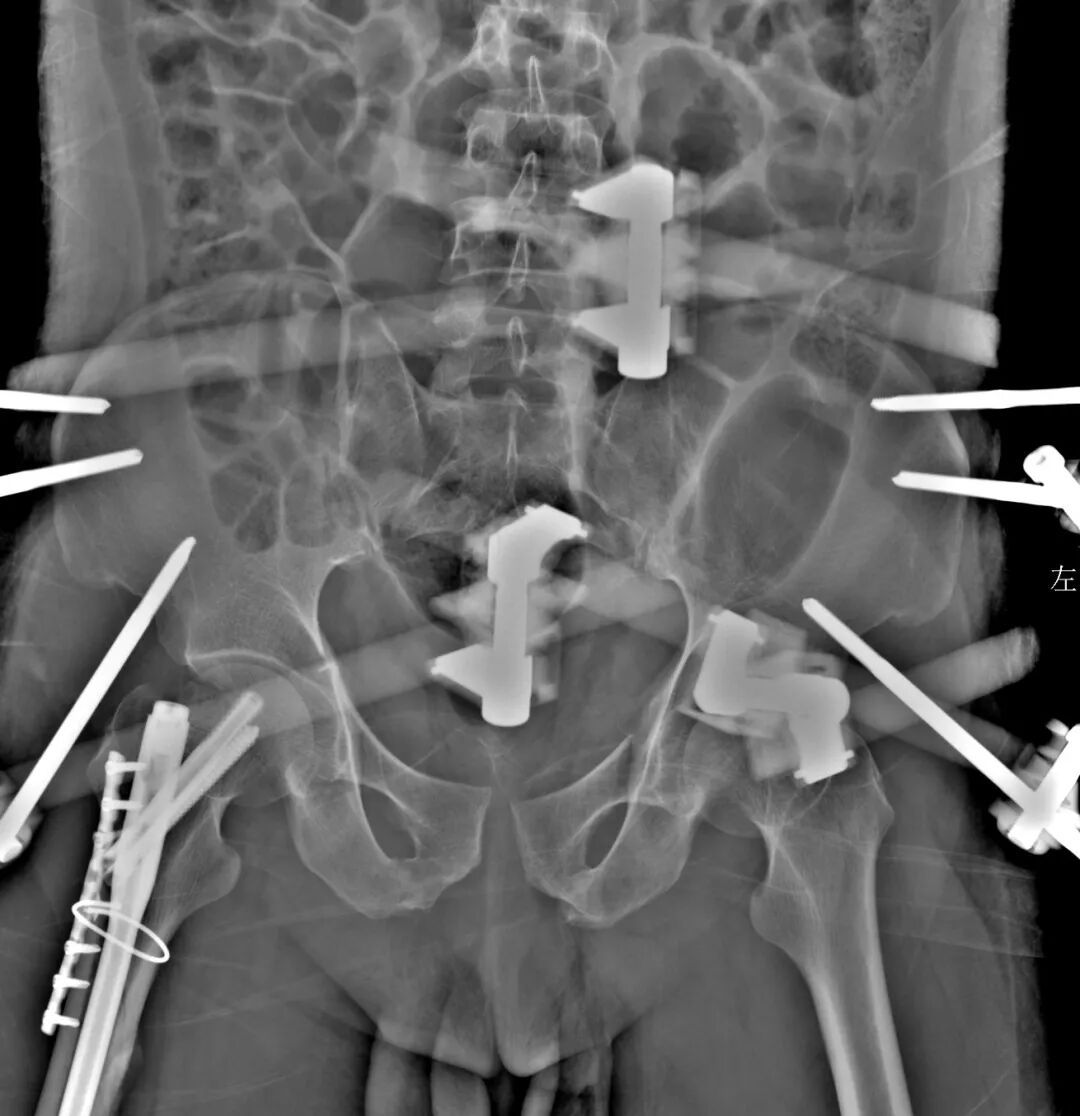

紧接着,骨科创伤值班组医生接力手术,为患者施行了骨盆外固定架固定术。该手术迅速稳定了严重不稳的骨盆环,有效减少了骨折端的继续出血和二次损伤,为患者的生命上了又一道“保险栓”。同时行胫骨结节牵引术稳定股骨骨较少骨折断端出血和软组织挫伤。术后,患者血压趋于稳定,被转入重症医学科(ICU)进行密切监护和高级生命支持。

骨科医生行骨盆外固定架固定术迅速稳定严重不稳骨盆环,减少骨折端继续出血和二次损伤

在ICU的严密监护和精心治疗下,患者的生命体征逐渐平稳,全身状况得到显著改善。待身体条件允许后,骨科团队为其进行了二期骨折内固定手术,对股骨等部位的骨折进行了更为稳固而精确的复位和内固定。在整个治疗过程中,泌尿外科、普外科等团队也针对各自的专科问题提供了精准的治疗,确保了患者各系统功能的恢复。

骨科医生行二期股骨多发骨折内固定手术